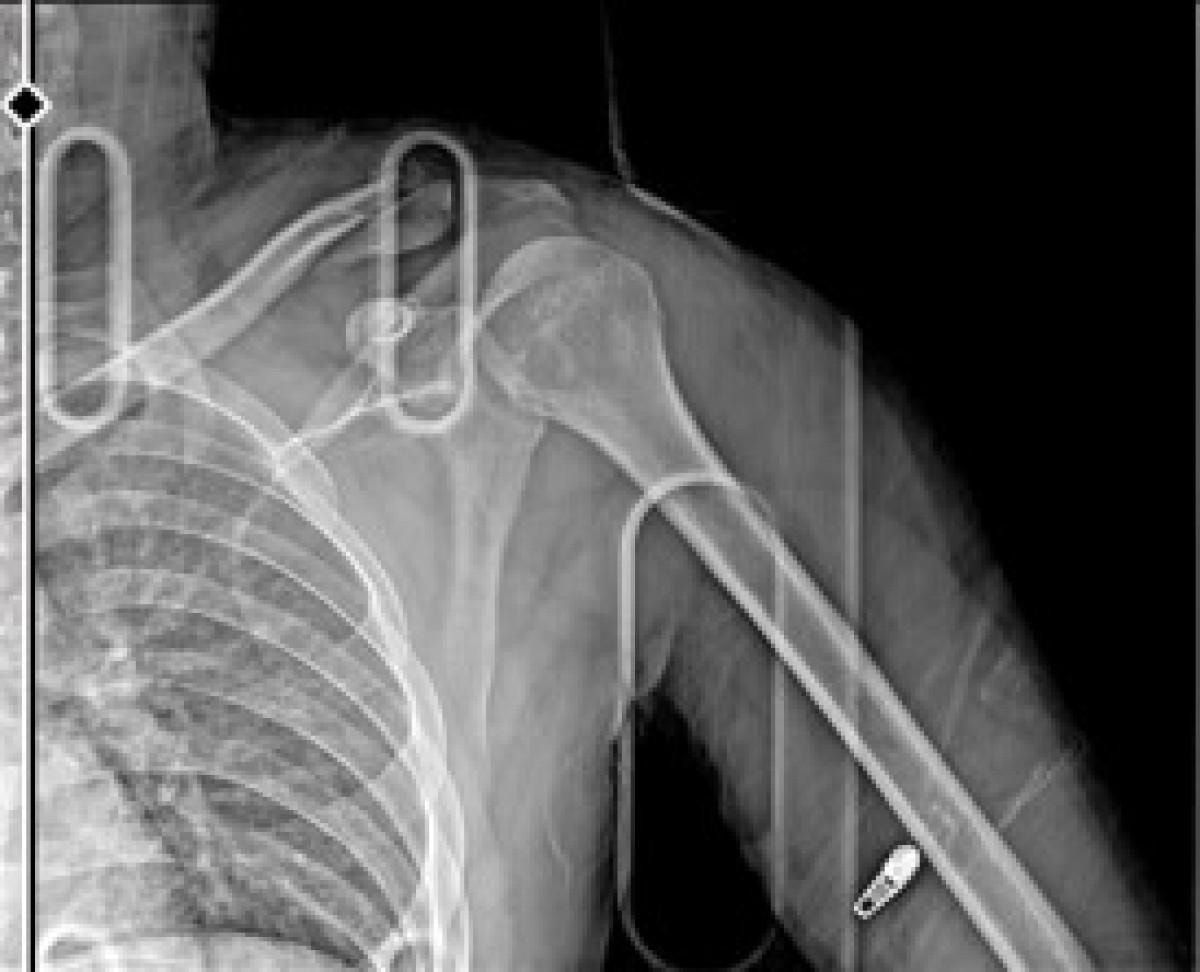

Çiçek, yaralı halde hastaneye kaldırılırken, sağ omzundan ameliyat oldu. Çiçek'in platin takılan kolunda kalıcı hasar oluştu. Hastanedeki tedavisinin ardından evinde istirahate çekilen Çiçek, işine devam edemeyeceğini ifade ederek, adaletin yerini bulmasını istedi. Çiçek, otomobil sürücüsü Y.Y.'den şikayetçi oldu.

Şu an koluma platin takıldı ve ömür boyu kalacak. İşimden oldum, motorum pert oldu. Motorum kullanılmayacak halde. O şekilde benim de 3-4 ay yatışım var. Sigortadan bir şey alamayacağım, benim çalıştığım yer buna müsait değil.